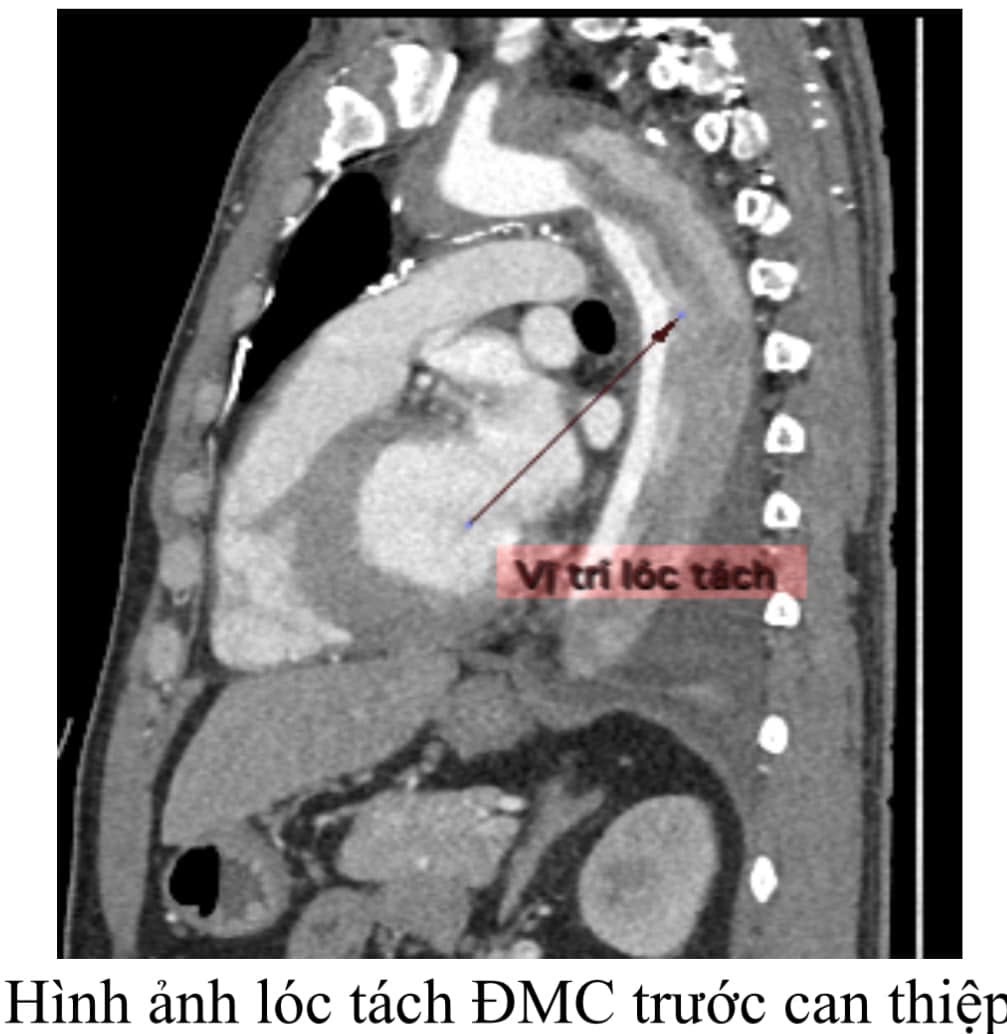

Bệnh nhân H.V.T (47 tuổi), có tiền sử tăng huyết áp không kiểm soát, nhập viện trong tình trạng đau ngực dữ dội. Qua thăm khám, các bác sĩ nhận thấy dấu hiệu huyết áp chênh lệch rõ rệt giữa hai tay (tay phải 200/110 mmHg, tay trái 160/90 mmHg) nghi ngờ lóc tách động mạch chủ ngực. Ngay lập tức, bệnh nhân được chỉ định chụp MSCT mạch máu, kết quả: lóc tách động mạch chủ ngực cấp tính lan xuống động mạch chủ bụng, nguy cơ vỡ động mạch và tử vong bất cứ lúc nào. Thật không may cho người bệnh vì giải phẫu vị trí lóc tách ngay sát động mạch dưới đòn trái, không đủ vị trí để đặt Stent Graft.